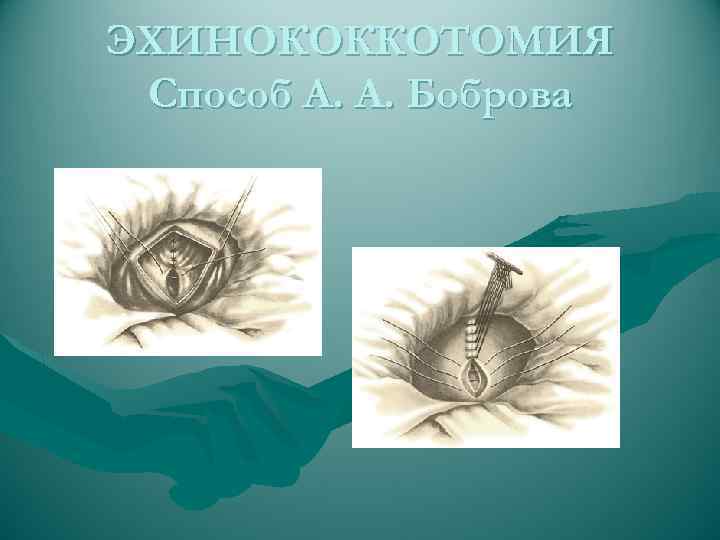

ЭХИНОКОККОТОМИЯ Способ А. А. Боброва

ЭХИНОКОККОТОМИЯ Способ А. А. Боброва